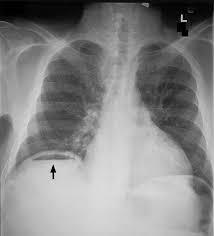

Complication de perfore et

peritonite dans les cas graves parfois se presentent

. Image de croisante gaseuse sous diapragmatique

droit d'une colite ischemique perfore |